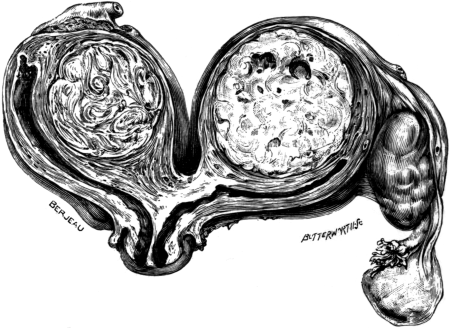

| 1. | Secondary Cancer of the Ovary | 15 |

| 2. | Secondary Cancer of the Ovary in Section | 15 |